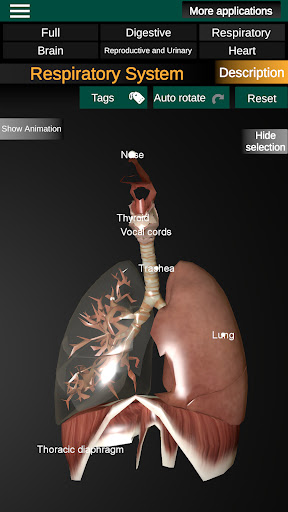

* Respiratory system, which includes the trachea, bronchi, lungs and an animation of this system.